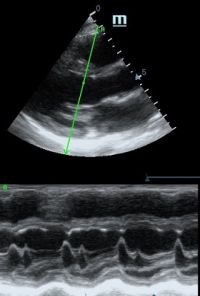

Оценка кооптации нижней полой вены ещё никогда не была такой простой и точной, никаких лишних деталей, просто устанавливаем клипер по анэхогенному участку.

Оценка сокращения сегментов левого желудочка на глаз постепенно уходит в прошлое. Если в приборе нет функции радиального или лонгитудинального стрейна, на помощь опять может прийти Free Xros. Утолщение более 5 мм в систолу – нормальное сокращение, 2-5 мм гипокинез, истончение в систолу – дискинез.